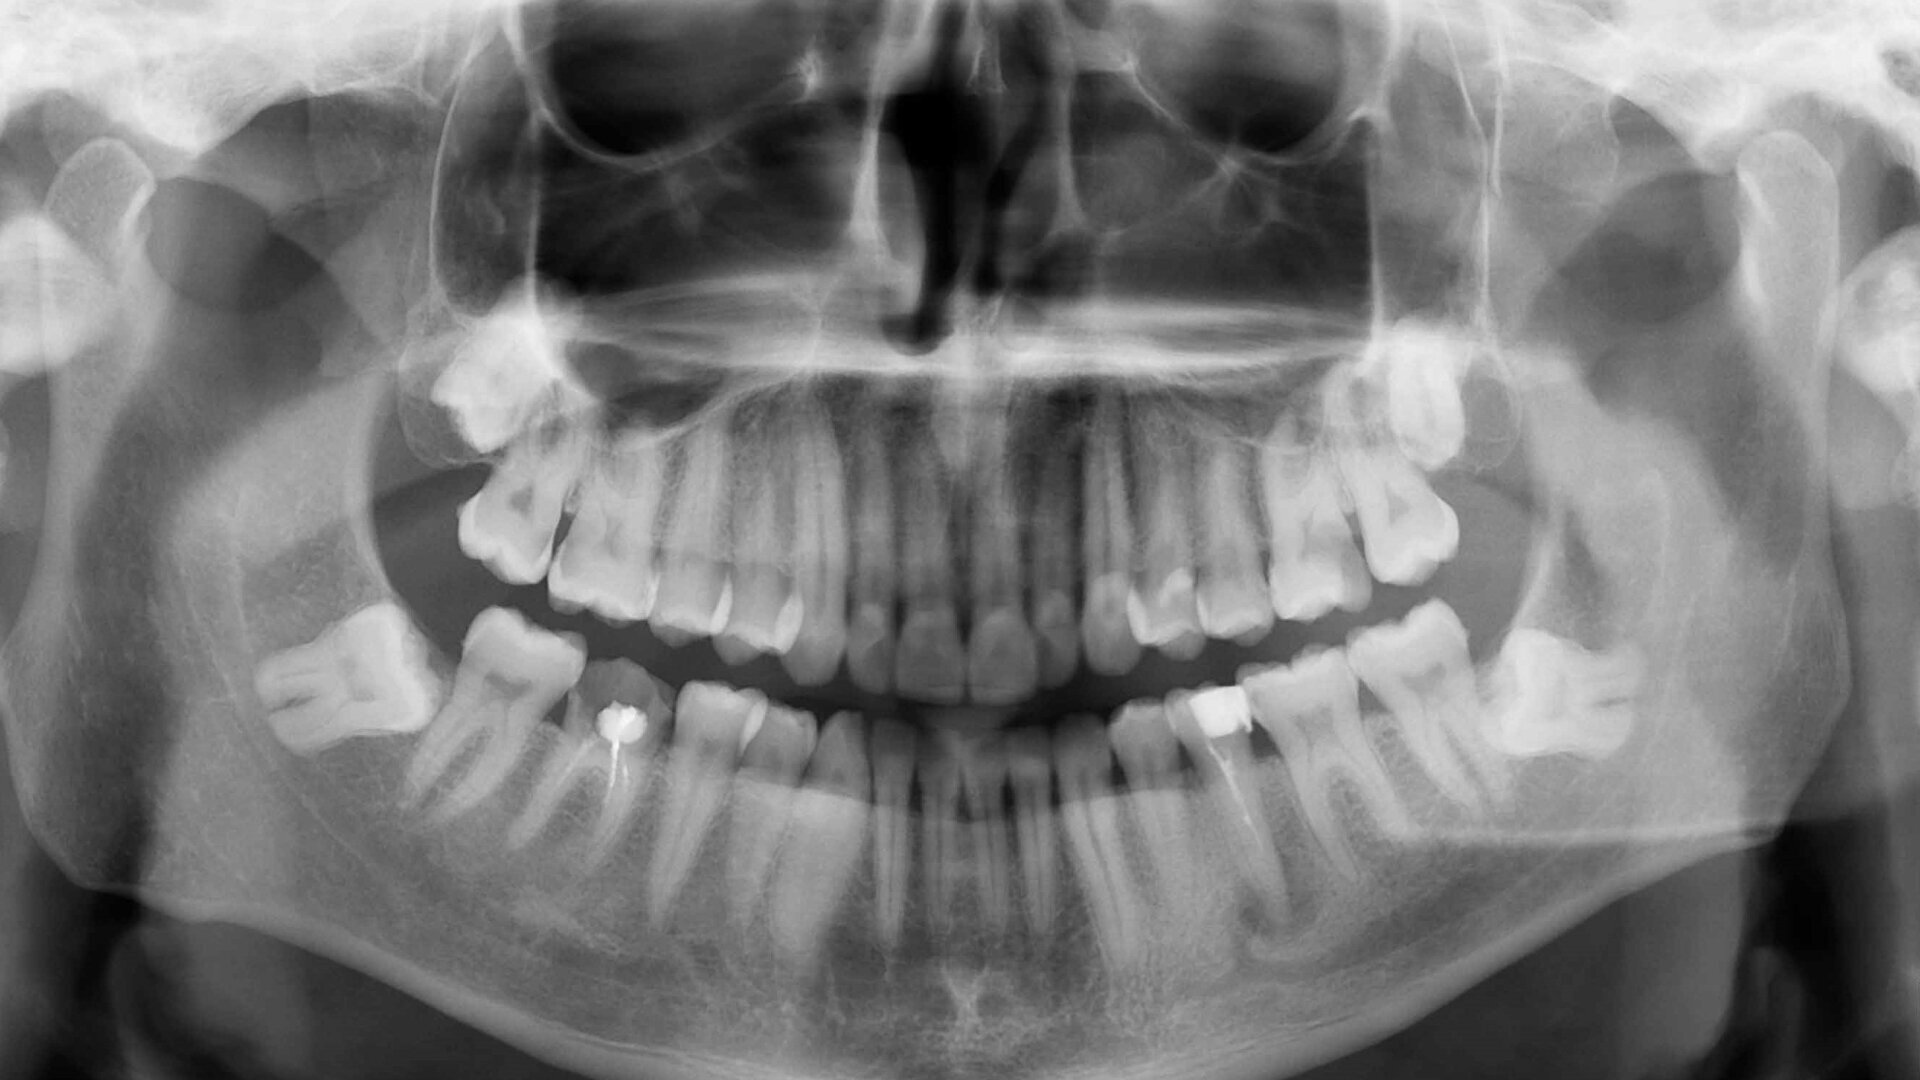

Fig. 1: Pre-op panoramic radiograph.

When the 40-year-old male patient was referred to our practice in the spring of 2018 with persistent complaints regarding the mandibular left second premolar, he was already rather frustrated. He had previously undergone several endodontic treatments at another practice, unfortunately without success. He was suffering from an acute periapical abscess and was in severe pain.

This was due to a special dental anatomy that had not been identified. In the middle of the root, about 13–14 mm from the cusps, the root canal split into two different canals (Vertucci Type V or deep split). This was easy to see on the initial panoramic radiograph (Fig. 1), which is why I decided to prepare the canals with HyFlex CM and HyFlex EDM files and under magnification (Figs. 2 & 3). This allowed me to follow the respective canal profiles and preserve the root canals as far as possible through optimal and centred preparation in each canal.